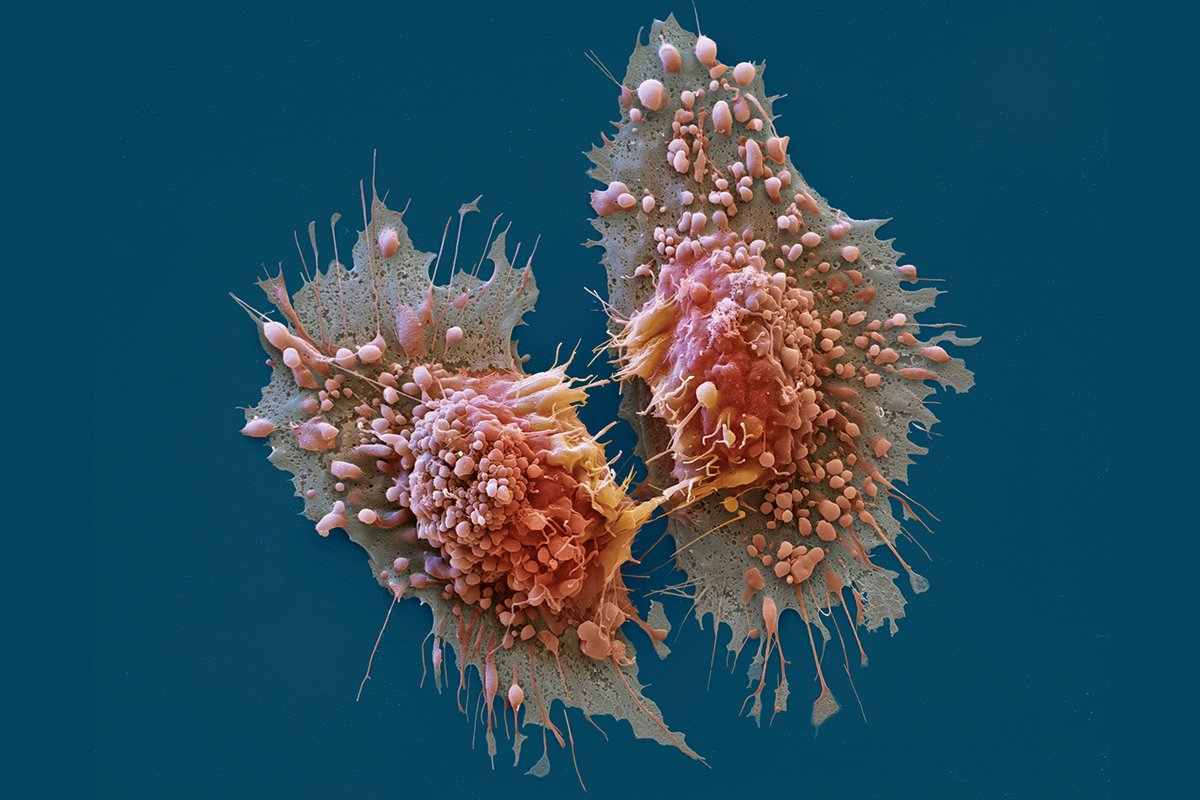

Раковая шишка – это заболевание, которое поражает кожу и слизистые оболочки. Она может возникнуть в различных частях тела и иметь различные внешние проявления. В данной статье мы представляем вам многочисленные фотографии раковых шишек, чтобы вы могли узнать, как они выглядят.

Одной из наиболее распространенных локализаций раковых шишек является лицо. На фото вы можете увидеть различные типы раковых шишек, такие как базалиома, плоскоклеточный рак и меланома. Обратите внимание на характерные признаки каждого типа раковой шишки, такие как изменение цвета, формы и размера.

Раковые шишки могут возникать не только на лице, но и на других частях тела. На фотографиях вы можете увидеть примеры раковых шишек на шее, руках, ногах и туловище. Обратите внимание на различные формы и размеры раковых шишек, а также на их внешний вид.